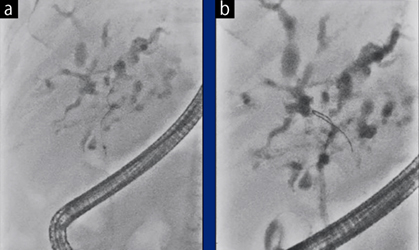

症例1:新画像処理条件により細径ガイドワイヤ

「ナビプロ0.025インチ」(ボストン・サイエンティフィック製)の視認性が向上

a:通常の透視像:ガイドワイヤが不明瞭

b:新画像処理条件の透視像:ガイドワイヤの視認性が向上